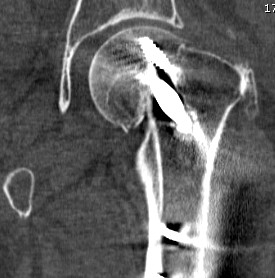

Synthes FNS (Femoral neck system)

Technique

Synthes FNS surgical technique guide